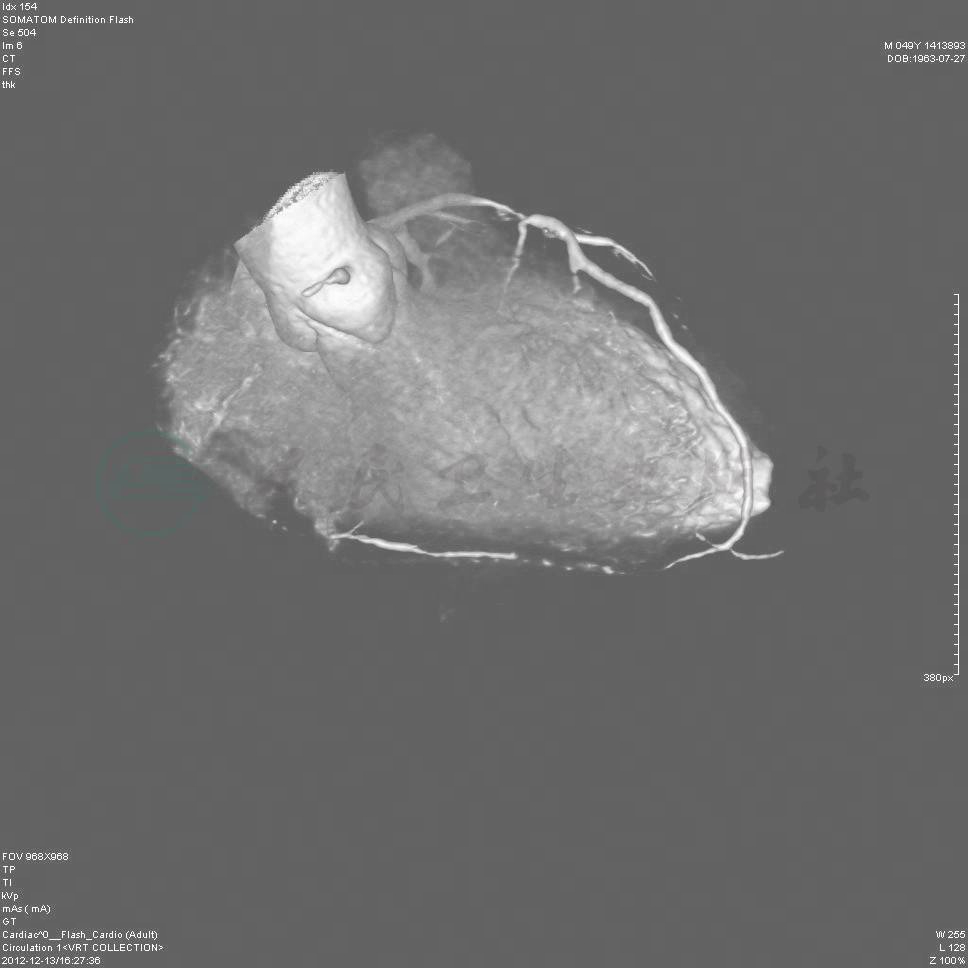

冠脉CTA:RCA近段起完全闭塞,LAD近段重度狭窄,LCX中段中度狭窄(图1~图4)。

图1 冠脉CTA提示RCA近段起完全闭塞(闭塞段很长),LAD近中段重度狭窄

图2 冠脉CTA提示RCA近段起完全闭塞

图3 冠脉CTA提示LAD近中段重度狭窄

图4 冠脉CTA提示LCX中段中度狭窄